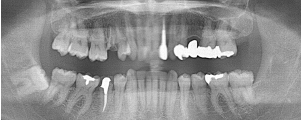

治療前のレントゲン

治療後のレントゲン

主訴は上の前歯の根元に違和感があるとのことでした。レントゲンを撮影したところ左上の2番目の歯の根元に大きな膿の袋が出来ており、保存不可能と診断、抜歯してジルコニアブリッジで治療することになりました。以前治療されていたセラミック冠の見た目も気になるとのとでした。問題のある根管治療はすべてやり直し、ファイバーコアを入れてから上下6歯をジルコニアオールセラミックで治療しました。ハグキの色も健康的になりました。